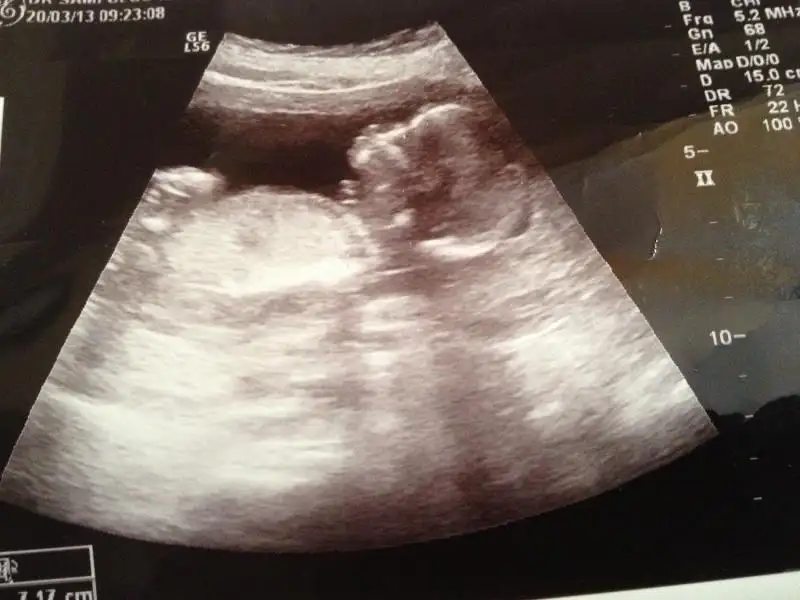

$241.webp $239.webp

bu da benim minik ORKİDEM yorum bekliyorum..yalnız eşim bilgisayarı akşam işe götürecek..saat 3 e kadar bakıcam inşallah o zamana kadar yorum yaparsın... ama yarın ilk iş buraya bakıcam..ORKİDEM yorumunu dört gözle bekliyorum.

burda 11hafta 6 günlük dayanamadım gittim. eşim hemen cinsiyeti sordu.dr a.dr dikişlerimden sezeryan olduğumu anladı ilk çocuğu sordu kız deyince kıyafetlerini attınız mı dedi hayır dedik bu da kız dedi.yani kız gibi görünüyo.dedi..pipisi çok küçükse onu bilemem.ama 15 gün sonra gelin daha kesin konuşurum dedi...

canim dr un kiz demis ama ilki kiz gibi ikinci resimm ise bariz erkekk